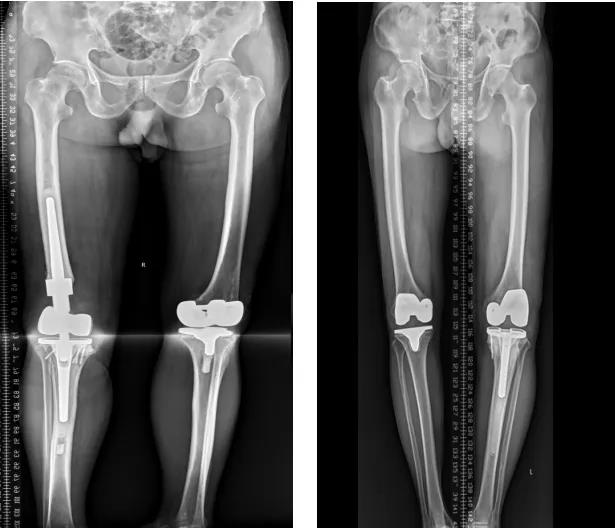

膝关节外科技术力量雄厚,科室配备医护人员30人,其中,主任医师5名,副主任医师3名,主治医师3名,住院医师4名,博士1名,硕士研究生4名。开放床位48张。该科擅长对膝关节严重创伤(包括股骨远端骨折、髌骨骨折、胫骨平台骨折等)、膝骨关节炎阶梯化治疗、保膝治疗、膝关节微创单髁置换术、全膝关节置换术、膝关节翻修术具有丰富的临床诊疗经验,追求微创、无痛、快速康复。对膝关节骨性关节炎采取阶梯化治疗方案,坚持中西并重、内外兼治的原则,取得满意的治疗效果。早期利用中医中药的传统优势,使用中医外治法,例如烫熨治疗、中药涂擦、雷火灸、中药塌渍等,同时辩证内服本院中药制剂及内服方药以及配合西药治疗,开展健康教育,运用运动疗法、物理治疗等辅助支持;中期开展软骨修复、截骨术、单髁置换术、髌股关节置换术等;对于终末期的膝关节OA采用全膝关节置换术。【膝关节外科主要特长】 (一)膝骨关节炎高位截骨术

(三)膝骨关节炎全膝关节置换术

(四)膝关节置换术后关节翻修术

(六)膝关节置换术后假体周围骨折内固定术